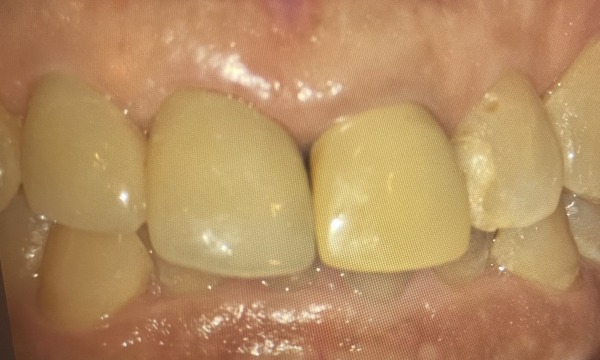

患者様は何十年振りに前歯をやりかえることになり、どんな被せ物ができてくるのかドキドキしていたそうです。色合わせや形までオーダーメイドで作ることがで きて、大変満足されていらっしゃいました。

今回の症例では、表側は『美しさ』を重視してセラミックに、裏側は『強度』を重視してジルコニアを使用しています。また、一度折れてしまった前歯を2本繋げることで、破損や脱離を防止しています。